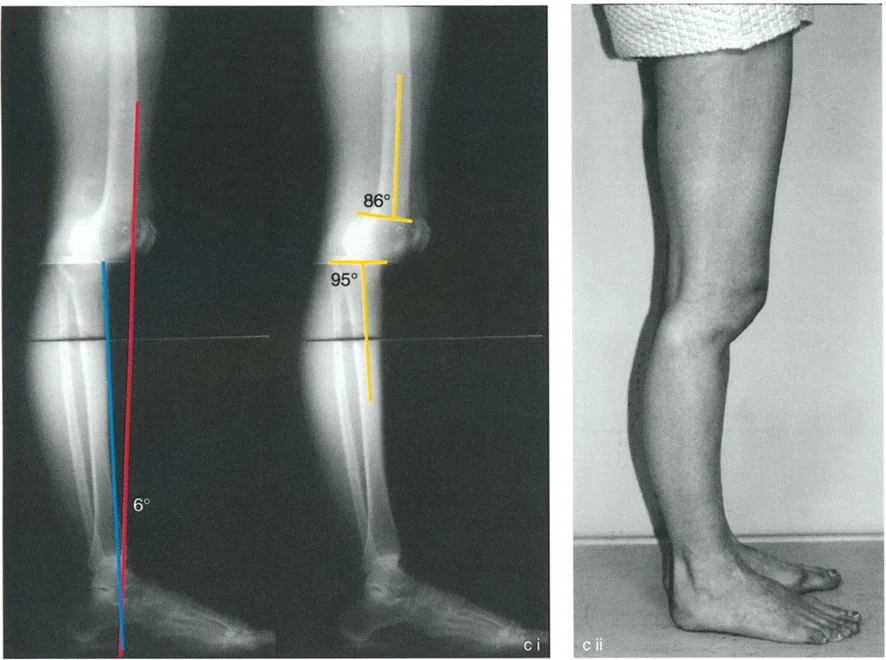

في المستوى السهمي، يجب أن تكون هناك زوايا محددة بين محاور العظام وخطوط المفصل لضمان توزيع متوازن للوزن واستقرار الأربطة. هذه الزوايا هي حجر الزاوية في مبادئ الدكتور بالي لتصحيح التشوهات:

- زاوية الفخذ الخلفية البعيدة (PDFA): وهي الزاوية بين المحور التشريحي لعظم الفخذ وخط مفصل الفخذ البعيد في المستوى السهمي. قيمتها الطبيعية حوالي 83 درجة.

- زاوية الظنبوب الخلفية القريبة (PPTA): وهي الزاوية بين المحور التشريحي لعظم الظنبوب وهضبة الظنبوب. تتراوح قيمتها الطبيعية بين 81 و 84 درجة.

توضح الصورة المحاور التشريحية والزوايا الطبيعية لعظم الفخذ والظنبوب، والتي تُعد أساساً لفهم تشوهات الركبة السهمية.

يتطلب التخطيط السليم تحديد خطوط العظام الطويلة وحساب قمة التشوه بدقة. وكما هو الحال في مبادئ محاذاة المحور، فإن تحديد خطوط منتصف العظم بالنسبة لخطوط توجيه المفصل هو الخطوة الأولى في تحديد مركز دوران الانحراف (CORA)، وهو النقطة التي يجب أن يتم عندها قطع العظم لتصحيح التشوه.

التقوس الخلفي في الجزء القريب من الظنبوب هو تشوه صعب بشكل فريد. على عكس الانحرافات الزاوية البسيطة، غالباً ما يؤدي التقوس الخلفي في الظنبوب القريب إلى خلع جزئي حقيقي خلفي للركبة.

عندما تميل هضبة الظنبوب إلى الخلف (مما يؤدي إلى زاوية PPTA عالية بشكل غير طبيعي، على سبيل المثال 95 درجة إلى 105 درجات)، ينعكس الميل التشريحي. يميل عظم الفخذ إلى الانزلاق للأمام على هذا الميل المعكوس، أو على العكس، ينخلع الظنبوب جزئياً إلى الخلف بالنسبة لقمة الفخذ. يخلق هذا عدم استقرار عميقاً، وعلامة سحب خلفي إيجابية، وآلاماً شديدة في الركبة الأمامية بسبب زيادة التحميل على آلية الباسطة.